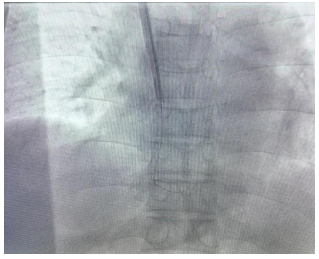

手术中

3年前,患者李先生,因慢性肾功能衰竭合并慢性心力衰竭等基础疾病长期在我院行血液透析治疗。因血管条件差,低血压,建立的动静脉内瘘血流量无法满足透析需求,行球囊扩张后血流量仍不理想,选择右颈内静脉隧道式透析导管作为血管通路也成了他唯一的生命通道。半年前患者逐渐出现导管功能不良,为建立安全有效的血管通路,与患者及家属充分沟通后办理入院,完善相关检查后,陈元姝主任医师、滕强主治医师为患者实施了“DSA引导下隧道式透析导管更换术”,手术顺利,导管尖端位置良好,术后引血通畅、血流量好,达250ml/min,能满足血液透析需求。

图为DSA引导下长期透析管置入

据肾内科主任陈元姝介绍,血管通路是血液透析患者生命线,隧道式导管也称长期透析导管是其中常见的长期血管通路,具有血流量好、感染率低、使用时间长等优点。如果出现导管失功、破损或者导管腔内感染无法治愈需要进行导管更换,DSA引导下置入是安全、有效的方法。通过DSA可视化精准操作,可提高置管安全性及手术成功率,避免血管及心脏损伤、心包填塞、导管移位、导管尖端不到位致功能不良等并发症。